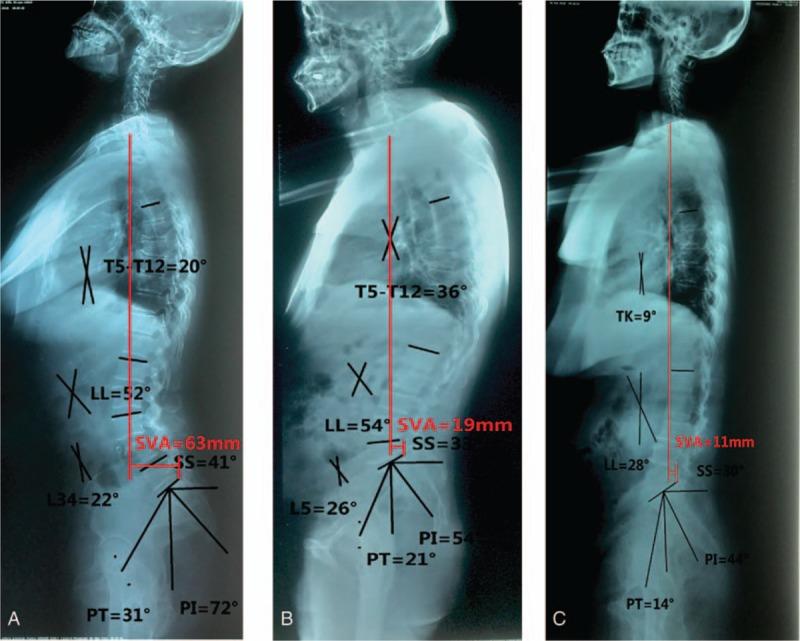

The purpose of our study is to evaluate sagittal parameters in 2-level lumbar degenerative spondylolisthesis (DS) (TLDS).A total of 15 patients with TLDS, 40 patients with single-level DS (SLDS), and 30 normal volunteers as control were included in our study. All subjects performed on full spine X-ray. Two categorized data were analyzed: patient characteristics-age, sex, body mass index, radiographic parameters-pelvic incidence (PI), pelvic tilt (PT), lumbar lordosis (LL), sacral slope (SS), PI-LL, Cobb between the fifth thoracic vertebral and 12th thoracic vertebral (T5-T12), sagittal vertical axis (SVA) Cobb angle of spondylolisthesis level (CSL), ratio of PT to SS (PT/SS), CSL/LL, variation trend of SS over PI, and LL over PI.The PI (73.1° vs 52.9°), SS (50.8° vs 32.2°), LL (53.1° vs 46.9°), SVA (66.1 vs 22.0 mm), PI-LL (20.0° vs 6.0°), and CSL (23.6° vs 20.0°) in TLDS were significantly larger than these in SLDS. The PI (73.1° vs 40.6°), PT (22.3° vs 17.1°), SS (50.8° vs 23.5°), LL (53.1° vs 32.5°), PI-LL (20.0° vs 8.1°), and SVA (66.1 vs 17.0 mm) in TLDS were significantly larger than those in the normal group (NG). The PI (52.9° vs 40.6°), PT (21.0° vs 17.1°), SS (32.2° vs 23.5°), LL (46.9° vs 32.5°), and SVA (22.0 vs 17.0 mm) in SLDS were significantly higher than those in NG. However, PT/SS (44.0%), LL over PI (y = 0.39x + 24.25), SS over PI (y = 10.79 + 0.55x) were lower in TLDS than these in SLDS (63.8%, y = 0.41x + 25, y = 0.65x - 2.09, respectively), and the similar tend between SLDS and NG (74.0%, y = 0.49x + 13.09, y = 0.67x - 3.9, respectively).Our results showed that 2-level lumbar DS, which was caused by multiple-factors, has a severe sagittal imbalance, but single-level has not any. When we plan for surgical selection for 2-level lumbar DS, global sagittal balance must be considered.

我们研究的目的是评估二级腰椎退行性椎体滑脱(DS)(TLDS)的矢状面参数。本研究共纳入15例TLDS患者、40例单节段DS(SLDS)患者以及30名正常志愿者作为对照。所有受试者均拍摄全脊柱X线片。分析了两类数据:患者特征(年龄、性别、体重指数)、影像学参数(骨盆入射角(PI)、骨盆倾斜角(PT)、腰椎前凸角(LL)、骶骨倾斜角(SS)、PI-LL、第5胸椎至第12胸椎(T5-T12)之间的Cobb角、矢状垂直轴(SVA)、椎体滑脱节段的Cobb角(CSL)、PT与SS的比值(PT/SS)、CSL/LL、SS随PI的变化趋势以及LL随PI的变化趋势)。TLDS患者的PI(73.1°对52.9°)、SS(50.8°对32.2°)、LL(53.1°对46.9°)、SVA(66.1对22.0mm)、PI-LL(20.0°对6.0°)和CSL(23.6°对20.0°)均显著大于SLDS患者。TLDS患者的PI(73.1°对40.6°)、PT(22.3°对17.1°)、SS(50.8°对23.5°)、LL(53.1°对32.5°)、PI-LL(20.0°对8.1°)和SVA(66.1对17.0mm)均显著大于正常组(NG)。SLDS患者的PI(52.9°对40.6°)、PT(21.0°对17.1°)、SS(32.2°对23.5°)、LL(46.9°对32.5°)和SVA(22.0对17.0mm)均显著高于NG。然而,TLDS患者的PT/SS(44.0%)、LL随PI的变化(y = 0.39x + 24.25)、SS随PI的变化(y = 10.79 + 0.55x)低于SLDS患者(分别为63.8%、y = 0.41x + 25、y = 0.65x - 2.09),且SLDS与NG之间有相似趋势(分别为74.0%、y = 0.49x + 13.09、y = 0.67x - 3.9)。我们的结果表明,由多种因素引起的二级腰椎DS存在严重的矢状面失衡,而单节段则没有。当我们为二级腰椎DS制定手术方案时,必须考虑整体矢状面平衡。